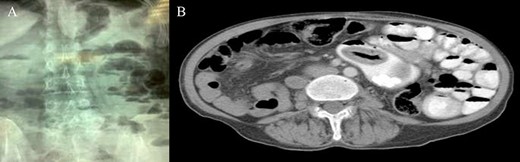

An upright plain X-ray of the abdomen was obtained and showed dilated small-bowel loops, mainly in the left upper abdomen, along with multiple air-fluid levels (Fig. 1A). The findings were compatible with small bowel obstruction. The etiology was then thought to post-laparotomy adhesions. The patient was admitted to the hospital and a nasogastric tube was inserted. Computed tomography (CT) scan of the abdomen and pelvis with oral contrast demonstrated a sac-like lesion of 105 cm in the left hemi abdomen containing oral contrast with multiple oval shaped macro-calcifications (Fig. 1B). A transition zone is noted at this level.

(A) Upright plain X-ray; (B) CT scan: sac-like lesion with macro-calcifications.